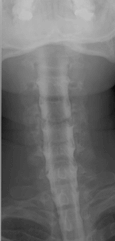

Die Myelographie ist ein invasives Verfahren an der Wirbelsäule. In der Neuroradiologie Heidelberg führen wir eine Myelographie jeweils nur zur weiterführenden bildgebenden Diagnostik bei Engen des Wirbelkanals oder der Nervenaustrittskanäle durch – also erst dann, wenn durch reguläre MRT- oder CT-Bildern nicht genaue Ergebnisse geliefert werden konnten. Vergleichen Sie hierzu unser gezeigtes Beispiel: